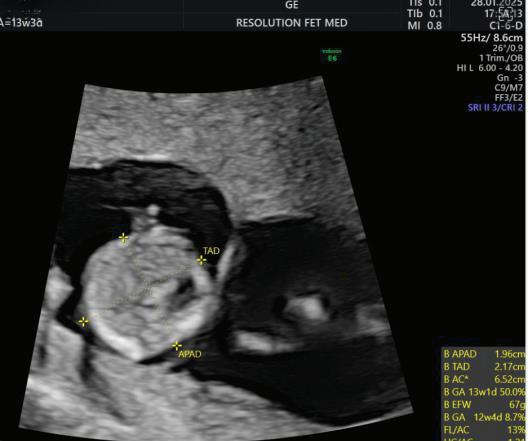

MEASUREMENTS THAT CAN BE OBTAINED ON

First Trimester Fetal Evaluation:

FETAL ULTRASOUND EXAMINATION AT 11 TO 14 + 0 WEEKS: BASIC BIOMETRY INCLUDES:

Nuchal Translucency

Biperital Diameter

(a) Crown Rump Length(CRL)

(b) Biperital diameter(BPD)

(c) Nuchal Translucency(NT)

DETAILED BIOMETRY INCLUDES:

Along with basic biometry

(a) Abdominal circumference

(b) Head circumference

(c) Femur length

Abdominal Circumference

1. NT is the sonographic appearance of subcutaneous accumulation of fluid behind the fetal neck, below the skin in the first trimester of pregnancy.

2. Measured in mid-saggital section only.

3. Measured between 11-14 weeks.

4. CRL between 45-84mm.

5. Magnified to include only head and upper thorax.

6. Fetus should be in neutral position.

7. Demostrate fetus separate from amnion.

8. Measurement should be ON to ON (cross bar of the callipers should be such that it’s hardly visible and merges with white line, not nuchal fluid).

During the scan more than one measurement should be taken and maximum value should be considered.